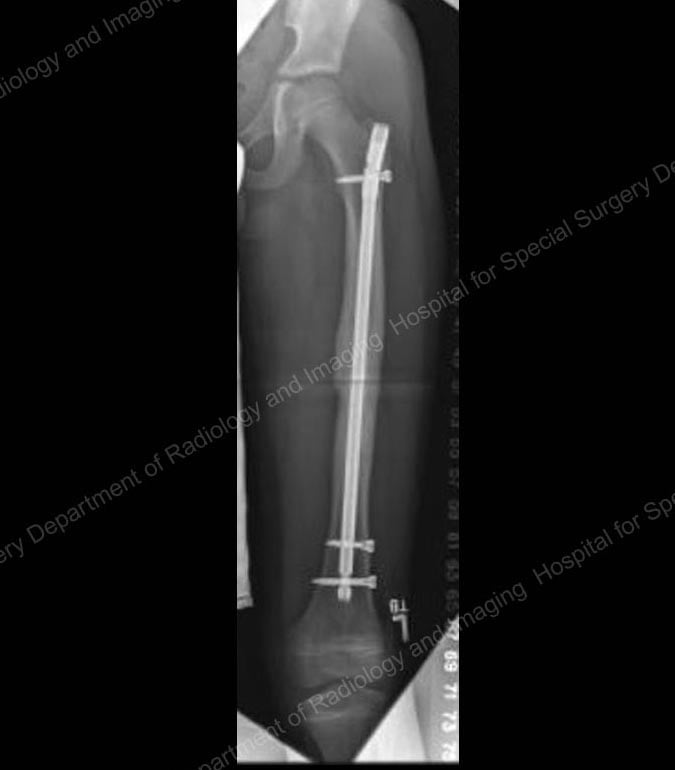

Treatment for older children and adolescents

Intramedullary nailing can also work well in older or heavier children, typically those over age 10 and heavier than 100 pounds. However, a single, thicker and more rigid nail is used rather than the smaller flexible nails.

In these children and teenagers, the nail is inserted through the top of the femur, near the hip, at a point called the greater trochanter, and locked into place with a screw at the top and the bottom of the bone. This placement avoids interruption of blood flow to the ball of the hip joint, which can lead to disabling arthritis. These concerns are not present in adults because they have different anatomy. In order to minimize the risk of complications when using intramedullary nailing in children, the orthopedist uses different devices and techniques than they would use in adult patients.

X-ray showing a rigid intramedullary nail in place.